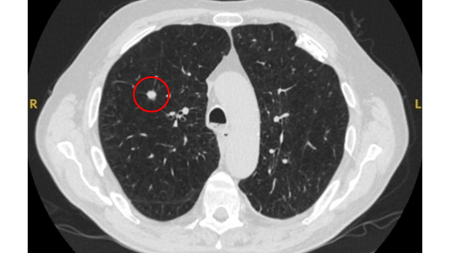

Taxa de crescimento

Um nódulo pulmonar solitário com crescimento bastante lento (tempo de duplicação do volume >500 dias) ou, paradoxalmente, um nódulo pulmonar solitário com crescimento muito rápido (tempo de duplicação do volume <30 dias) sugere uma etiologia benigna, embora esta não seja uma regra absoluta. A ideia tradicional de 2 anos de estabilidade confirmando uma doença benigna é razoável para nódulos pulmonares solitários. No entanto, ela foi questionada e deve ser usada com cautela em casos de opacidade em vidro fosco.[27] O médico deve ter em mente que um aumento de aproximadamente 30% de diâmetro de uma lesão esférica na radiografia representa uma duplicação do volume.[28]

As diretrizes do Reino Unido fazem as seguintes recomendações em relação à taxa de crescimento:[4][29]

Nódulos sólidos: um tempo de duplicação do volume >600 dias não requer acompanhamento, enquanto um tempo de duplicação do volume <400 dias, ou crescimento nítido definido como um aumento de 25% ou mais no volume, sugere a necessidade de investigações diagnósticas.[Figure caption and citation for the preceding image starts]: Tomografia computadorizada (TC) mostrando nódulo solitário espiculado no lobo superior direito dentro de enfisema, em fumante atual com exposição prévia ao amianto. Observe a placa pleural visível no lado esquerdo. A histologia da ressecção revelou adenocarcinoma do pulmãoDo acervo de Dr. George Tsaknis, MD, PhD, FRCP (Londres), MRQA, MAcadMEd, PGCert; usado com permissão [Citation ends].